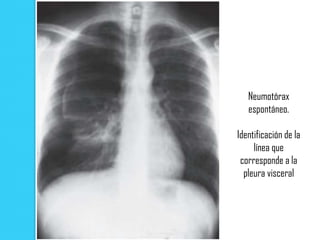

Neumotórax

espontáneo.

Identificación de la

línea que

corresponde a la

pleura visceral

Neumotórax espontáneo. Identificación de la línea que corresponde a la pleura visceral